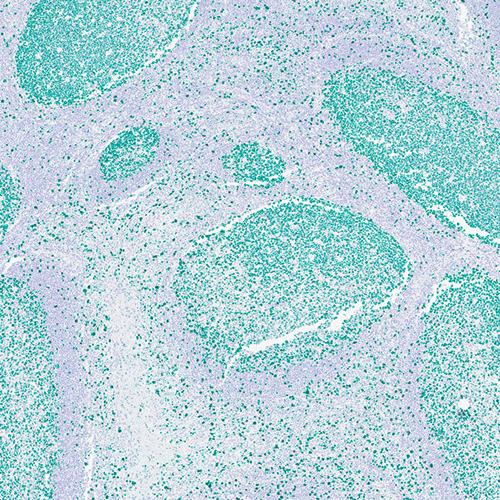

Green Chromogen is designed to be used in conjunction with DS9914 BOND Polymer Refine HRP Plex Detection kit. This chromogen provides an intense green color and is suitable for use with permanent mounting media such as our CV Ultra mounting media.

Our Green Chromogen can be used to provide striking contrast against a multitude of chromogen and counterstain staining combinations. Take advantage of on-board chromogen mixing on BOND instruments, not to mention the fully automated staining opportunities using BOND detection systems and BOND ready-to-use primary antibodies and probes.